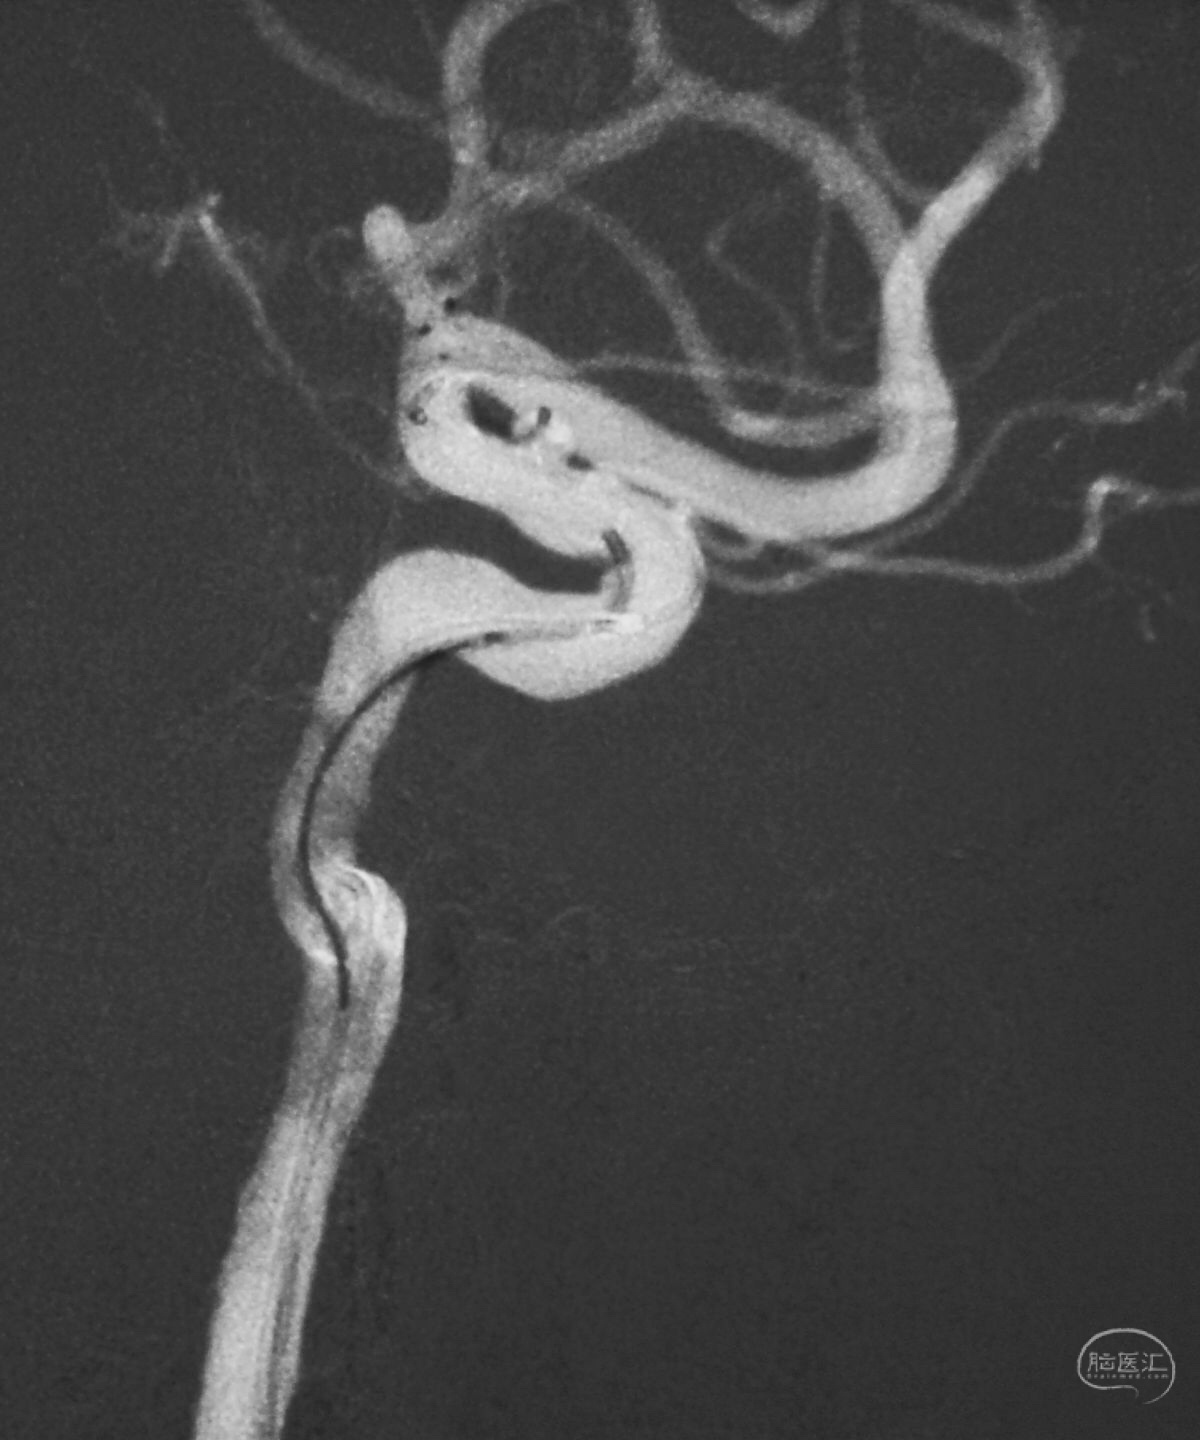

Echelon 10微导管头无论塑成C形还是S形,均无法稳定于动脉瘤腔内,遂使用回马枪技术,使微导管成襻通过,管头折返入瘤腔。

跨瘤颈释放Solitaire 4×20支架(蓝线),压住微导管(红线),在支架保护下经返折的微导管送入弹簧圈填塞瘤腔。

依次送入QC-2-4-3D,2-3-Helix,1.5-2-Helix,1.5-2-Helix四枚弹簧圈,最后一枚弹簧圈将管头(箭头)顶出瘤腔。